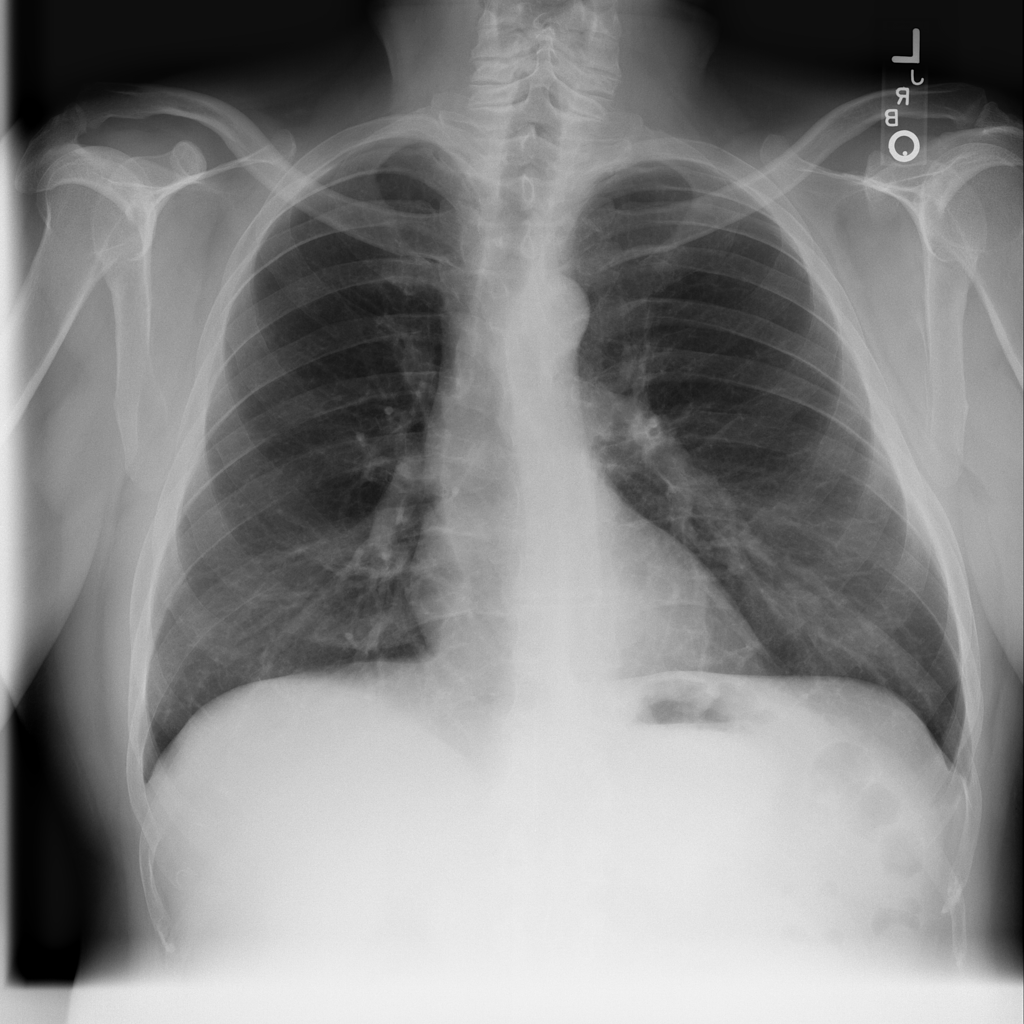

PAT-894B · IMG-000Emphysema

PAT-894B · IMG-000

PA